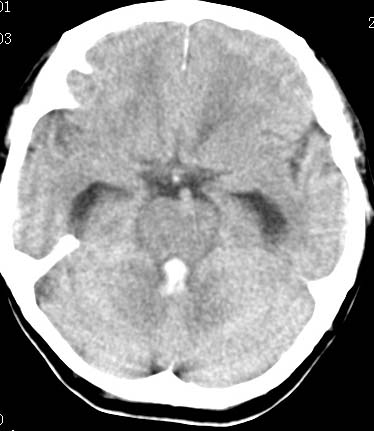

男性 病人 请大家看看出血的部位究竟在哪里?

是不是脑室系统出血啊! 伴轻度脑积水! 请老师指教!!

原发性脑室出血!

脑室系统出血,并脑积水.

我觉得是左侧侧脑室体旁出血,破入脑室系统.理由:除了左侧脑室体部外缘不规则之外,还有就是左侧脑室里面出血量较右侧多!

应该是左侧侧脑室内的出血导致其他脑室内的积血。

应该是尾状核出血破入侧脑室.

1、原发脑室出血,出血部位应该是左侧侧脑室;

2、左侧基底节区腔隙性脑梗塞;

(不考虑脑积水,脑室急性出血期脑室系统会轻度扩张)

脑室系统出血,第三脑室,侧脑室都有

出血点在左侧脑室旁。

左侧尾状核体部出血破入脑室系统.

最重要的是要讲明以脑室内积血为主,脑积水